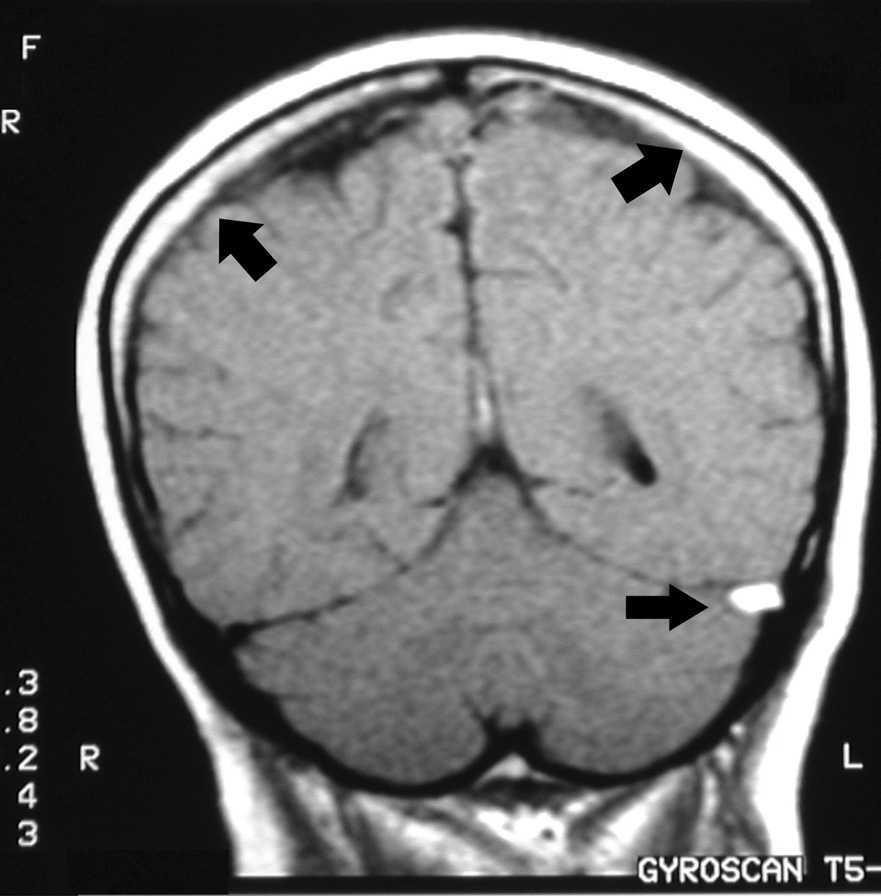

Figura 2. Imagen potenciada en T1, hiperdensidad en ambas regiones talámicas